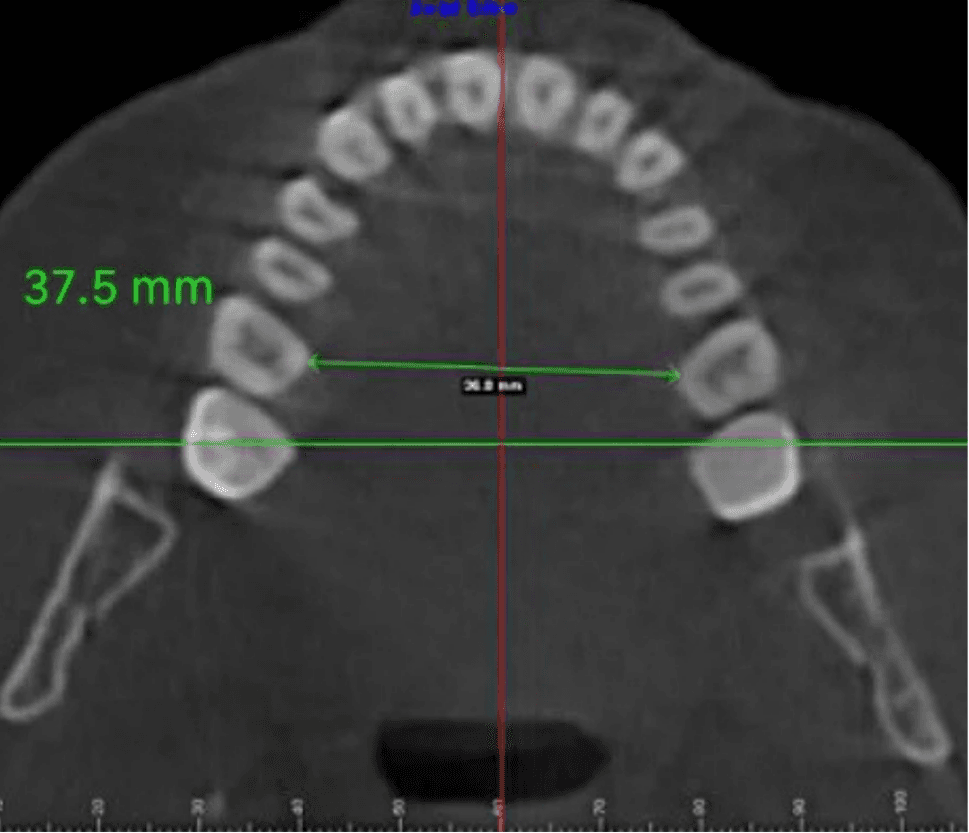

Dr. Tara Griffin is a Vivos provider who underwent treatment herself. She was diagnosed with moderate obstructive sleep apnea in 2011, with an AHI of 24 events per hour. What distinguishes her case is the depth of documentation: her progress was tracked not only by sleep studies but by direct measurement of her dental arch, the structural width of the upper jaw, over the course of eight years. Her arch measured 31.5 millimeters before treatment. By 2013, after approximately 10 to 15 months of treatment, it had expanded to 35.5 millimeters. At her 2019 follow-up, 37.5 millimeters.

Jaw Width - 37.5mm

Follow-Up, 2019